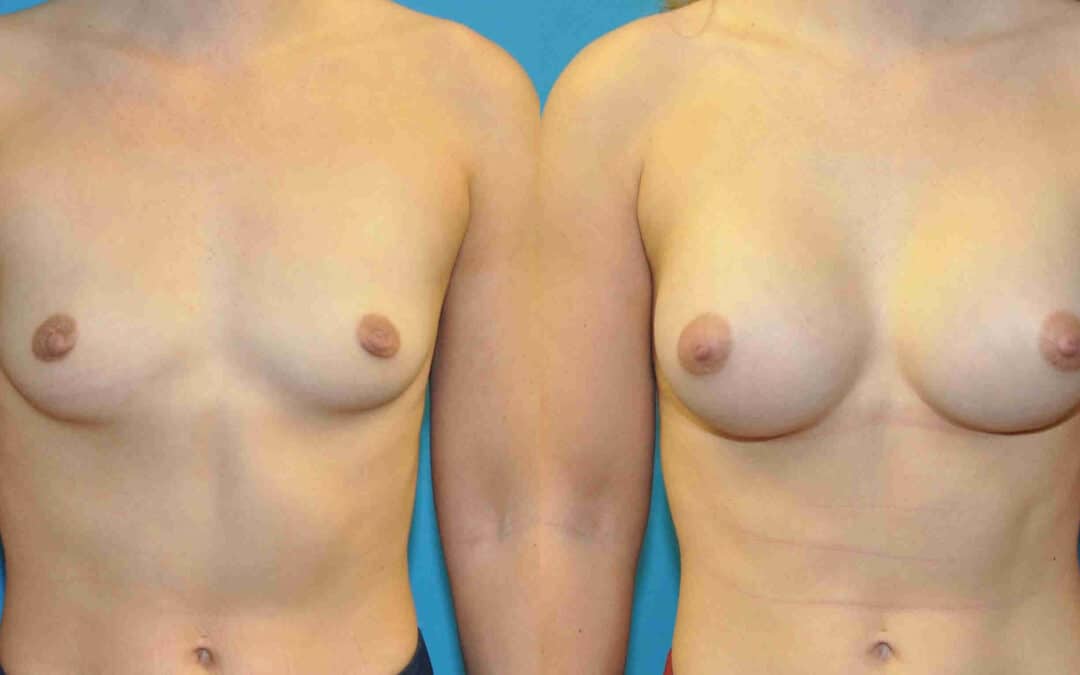

This 23 year old female dislikes the low profile appearnace of her breast shape. A 295 cc smooth round silicone implant was placed using a dual-plane technique. The result is a natural appearance along the upper pole of each breast and a rounder shape with more projection. She is delighted with her new look.